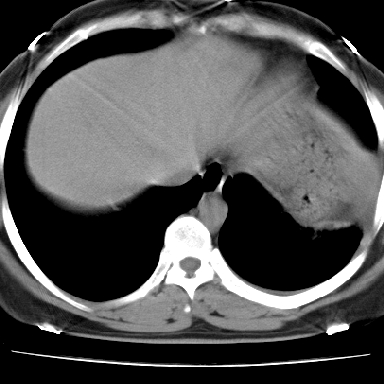

左下肺肿块影,内可以见小泡征,并见厚壁空洞形成,洞内缘可见壁结节。靠近胸膜侧可见胸膜肥厚粘连。双肺可见多发性小结节影。

考虑:左下空洞性肺癌伴两肺转移

左下肺有空洞,壁厚薄不均,壁结节,两肺多发小结节影,腋窝下可疑淋巴结肿大,综上所述考虑周围性肺癌并两肺转移可能性大,建议穿刺活检。